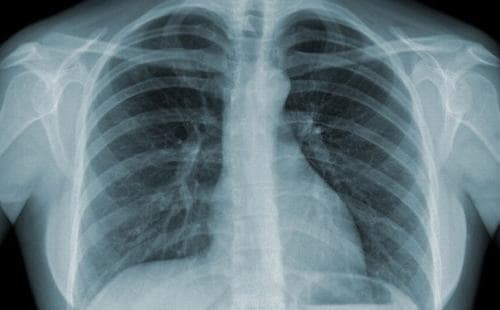

- Nếu nghỉ ngờ bị thấp tim, cần chụp X quang và làm các xét nghiệm cận lâm sàng khác để kiểm tra

+X quang tim phổi